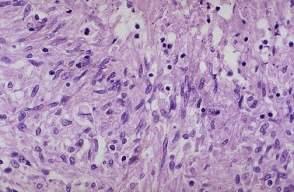

261.如图所示,结核结节主要由什么细胞构成